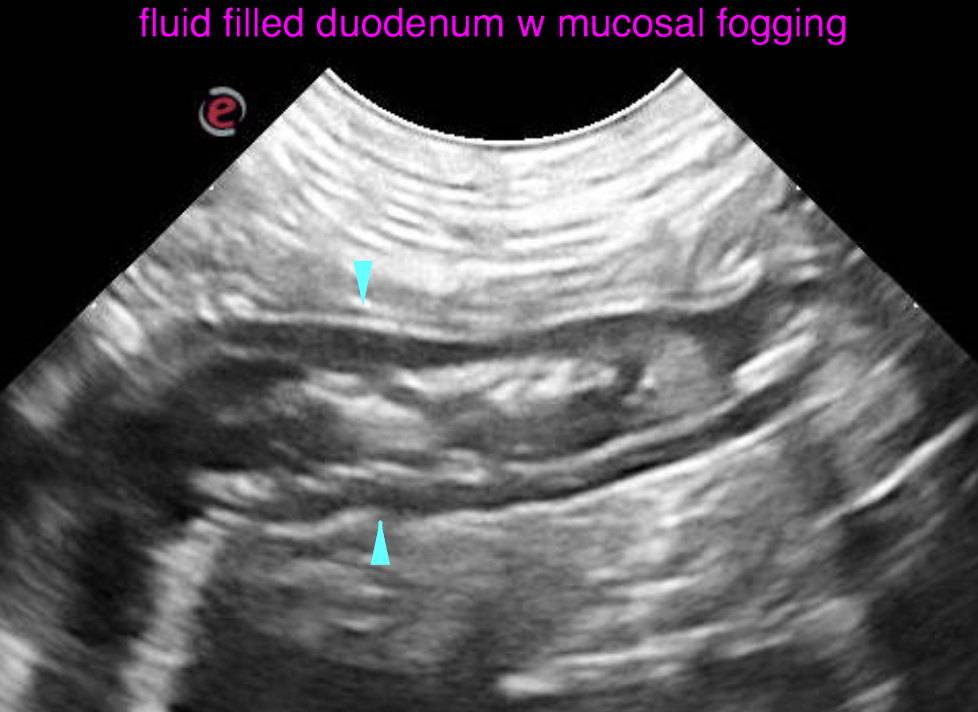

The left and right lobe of the pancreas are embedded in a slightly hyperechoic mesentery, but within normal limits for size, shape and echoarchitecture.  The gastric wall presents moderate generalized wall thickening emphasizing the submucosal layer. The interrugal wall thickness is up to 5 mm. The wall layering is moderately obscured. The mucosal surface is slightly irregular. A moderate amount of fluid is present within the stomach. The surrounding mesentery is mildly increased in echogenicity with slightly ill defined echotexture. The stomach is hypomotile. The duodenum is slightly dilated with fluid, presents hypermotility and mucosal fogging. The wall layering is witho normal limits. The jejunum presents similar changes as the duodenum. There is no obstructive pattern of the digestive tract.